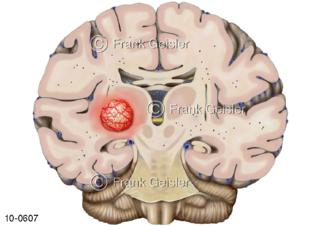

Bildergalerie Nervensystem

Bilder zum Nervensystem,dem Gehirn, Teil des zentralen Nervensystem, Zentralnervensystem ZNSmit Rückenmark, Abbildungen zum Nervengeflecht (Nervenplexus), die Verflechtungen von Nervenfasern, aus der Wirbelsäule hervortretende Nervenäst sowie Nervenzellen der Nerven